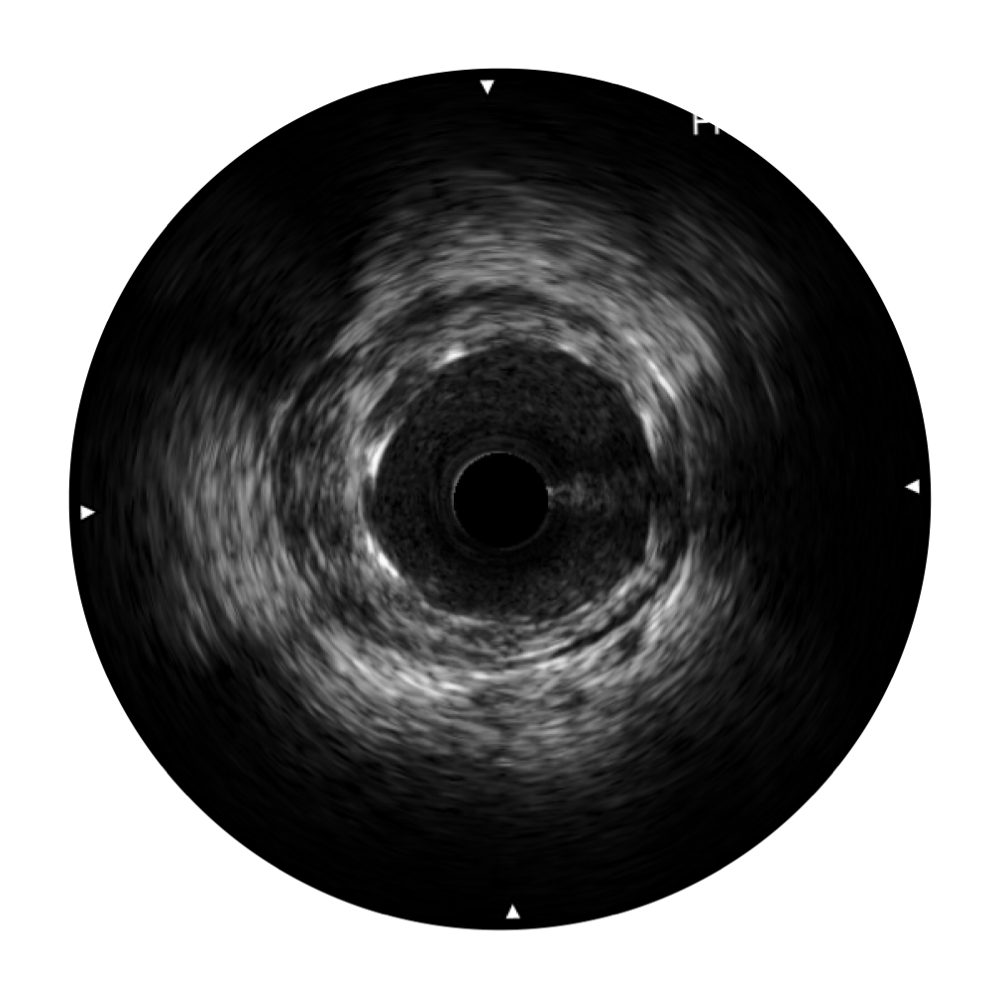

玖鼎集团宽频IVUS图像

对比传统IVUS导管成像,玖鼎集团宽频IVUS图像的近场支架梁显影更细腻,远场中膜外血管仍清晰可辨,兼顾远中近,兼顾分辨力与穿透深度